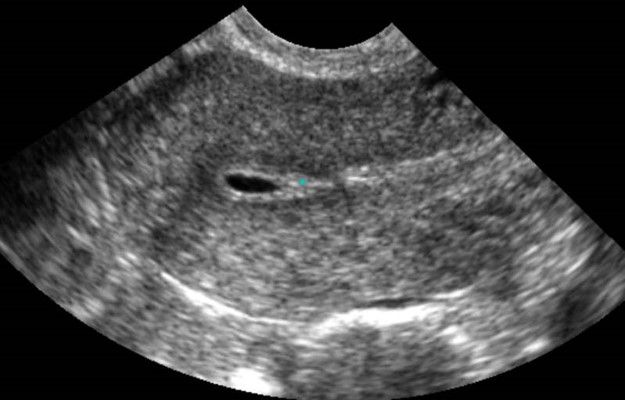

Современные экспертные УЗИ сканеры дают возможность проводить исследования всех органов в 3D. Это позволяет, используя полученный массив данных, получать диагностические сечения в любой плоскости, недоступной для обычного 2D УЗИ. Наиболее интересной является фронтальная. Например, визуализация полости матки. Диагностическая возможность выявления пороков развития превосходит все другие методы (рентгеновские и МРТ). Метод также позволяет уточнить положение ВМК (спирали) в полости матки, расположение миоматозных узлов, расположение плодного яйца на малых сроках, полипов. Сегодня современное экспертное ультразвуковое исследование невозможно без использования 3D УЗИ.